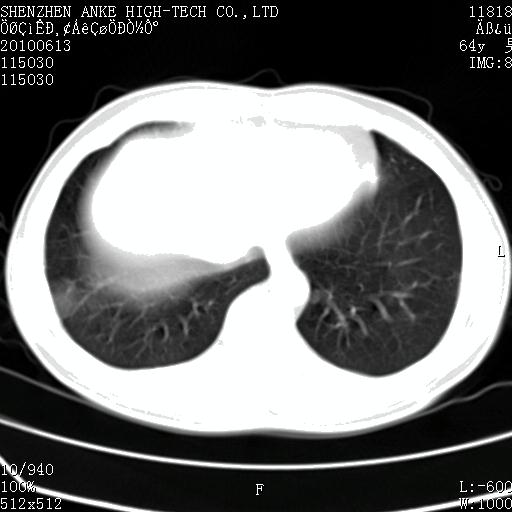

以下是引用beifangren在2010-7-26 22:05:00的发言:[br]左肾中极圆形占位,肾盏肾盂受压移位,建议增强。结合肺部结节。肝低密度灶,多为肾癌并肺部、肝转移。